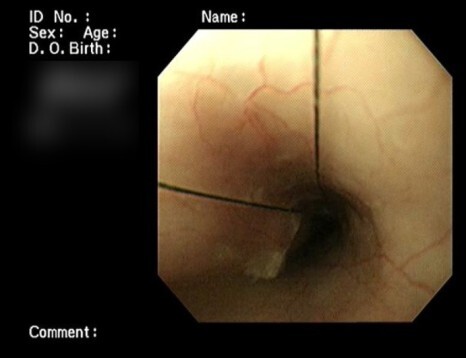

내시경 검사에서 식도부터 위까지

위에서도 십이지장까지 끈이 지나가는 것을

확인할 수 있었습니다.

위부터 소장까지 걸려있는 것은 확인하였으나

식도 쪽 말단 부를 확인할 수 없어서

구강을 다시 확인하였습니다.